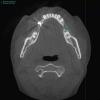

SergeyAL Опубликовано 27 мая, 2013 Поделиться Опубликовано 27 мая, 2013 у пациентки трехмерный костный дефект далее проведена трехмерная костная пластика, доступ латеральный тоннель рана ушита послойно получен хороший объем костной ткани получена костная ткань хорошего качества, хорошо кровоснабжаемая 5 Ссылка на комментарий